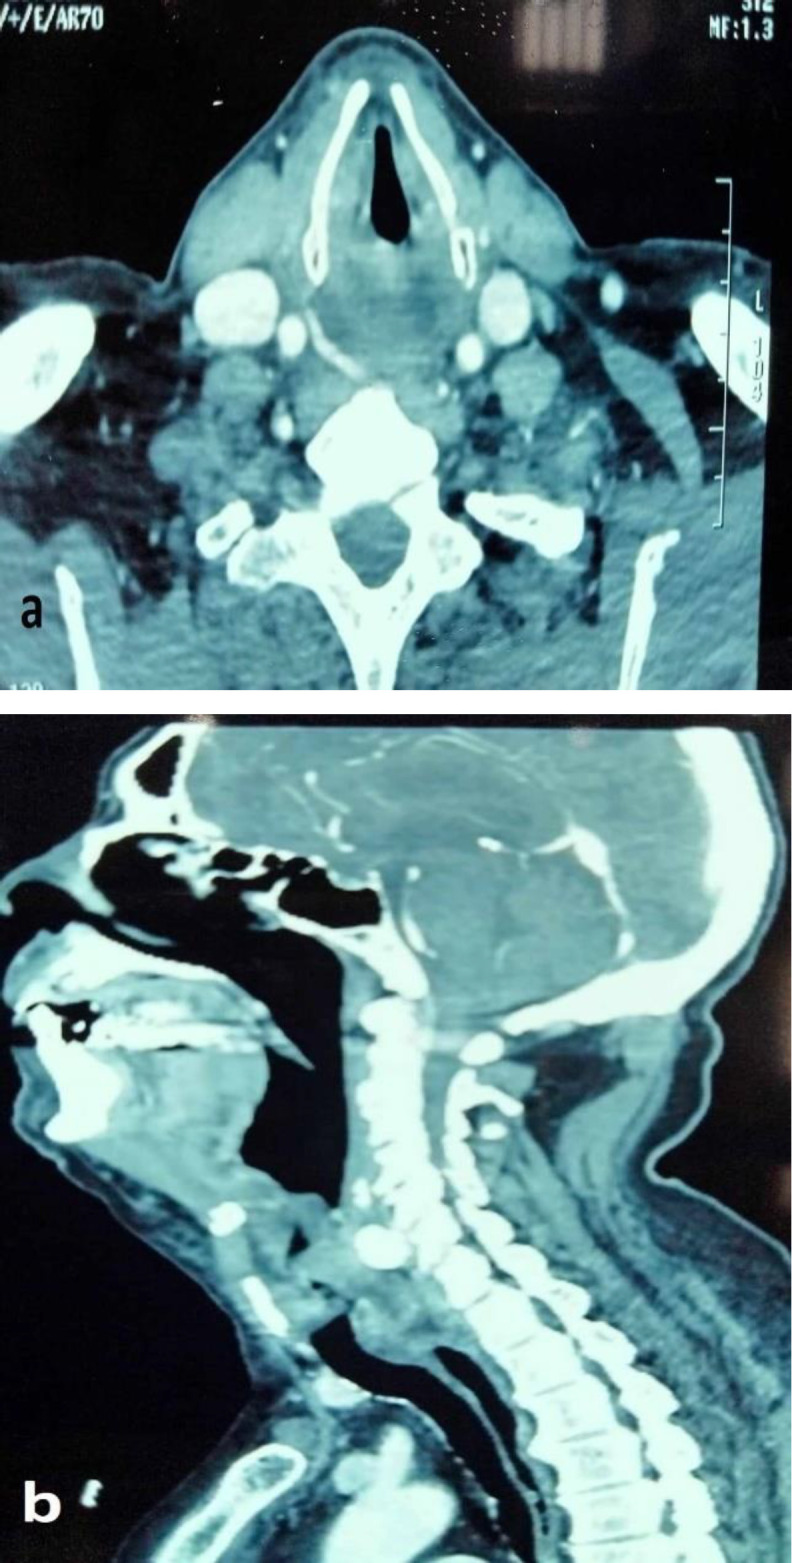

Case report: We present the case of a 74-year-old man who was on oral anticoagulation by acenocoumarol and presented with acute laryngeal dyspnea. The final diagnosis of pharyngo-laryngeal hematoma secondary to hypercoagulation was made based on the clinical, biological, and radiological features. Therefore, conservative management was initiated. Drug interactions between anticoagulants and macrolides were the probable underlying causes of excessive anticoagulation.